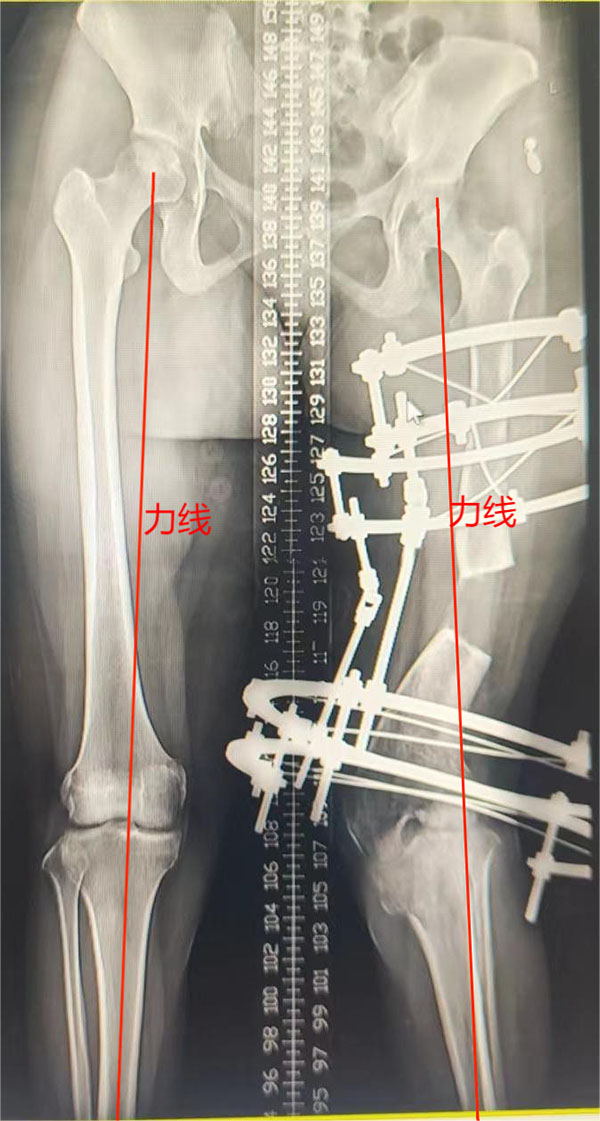

第一步:行左股骨远端截骨+Illizarov外固定架固定矫形延长术,术后通过每日定量的调整Illizarov外固定架上的延长杆,达到矫正肢体畸形的目的(此过程大概需要4-6个月)。

第二步:经过第一步的治疗,左下肢外翻畸形基本纠正,力线恢复,尽早拆除Illizarov架,予行切开钢板内固定术。

▲术前畸形,拆除外固定架,钢板内固定

术后半年,力线恢复